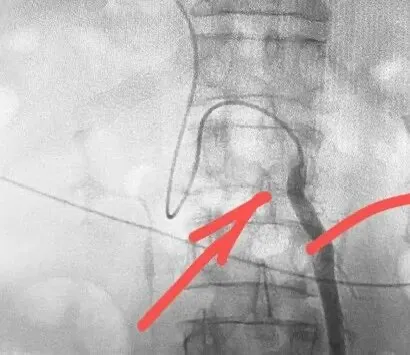

术中造影复查显示,支架位置精准、分流通畅,患者门静脉压力显著下降,肝动脉等重要血管未受任何损伤,手术全程历时2小时,最终圆满成功。

血管塞堵塞后↑